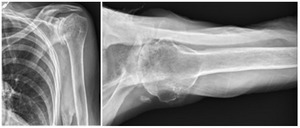

Case two is an 86-year-old female with long standing left shoulder pain and loss of function. Preoperative exam shows 70° of active forward flexion, neutral external rotation, and internal rotation to the lateral thigh. Radiographs (Figure 5) and CT scan (Figure 6) show significant posterior bone loss and retroversion with medialization of the joint line. Options include asymmetric reaming, an augmented component, or bone grafting. An augmented reverse baseplate was selected for this elderly female. Radiographs at six months show a well fixated baseplate with improvement of the pre-operative retroversion (Figure 7).